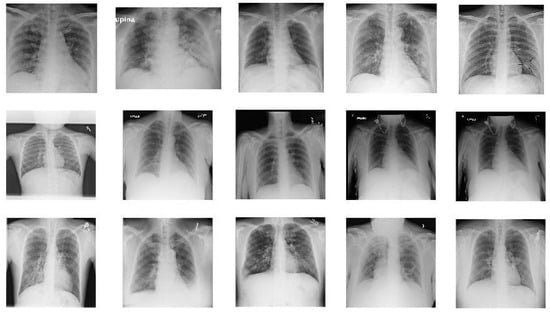

In this paper we used two different datasets which are available online. The first dataset is on chest X-ray images (see Figure 1) and the second on CT scans of lungs (see Figure 2).

The first dataset used was selected from [35] and is composed of X-ray images. This was collected from two different sources and contains images of three classes: COVID-19, Pneumonia, and No-findings.

One of these sources was developed by Cohen JP [36], who provided the COVID-19 X-ray images using various open access sources. There are 127 X-rays with COVID-19 in the database, where 43 belong to females and 82 to males with a positive diagnosis.

The other source is the ChestX-ray8 database provided by Wang et al. [37]. ChestX-ray8 is composed of 108,948 frontal view X-ray images with different pathologies. In this study, and as it is used in [35], to avoid the imbalance data problem and due to the reduced number of COVID-19 images, we used 500 no-findings and 500 pneumonia class front chest X-ray images randomly from this database.

Figure 1. Sample images from X-ray dataset. The images in the first row show 5 COVID-19 images. The images in the second row are 5 sample images of no-finding category in Non-COVID images. The images in the last row give 5 sample images from Pneumonia.